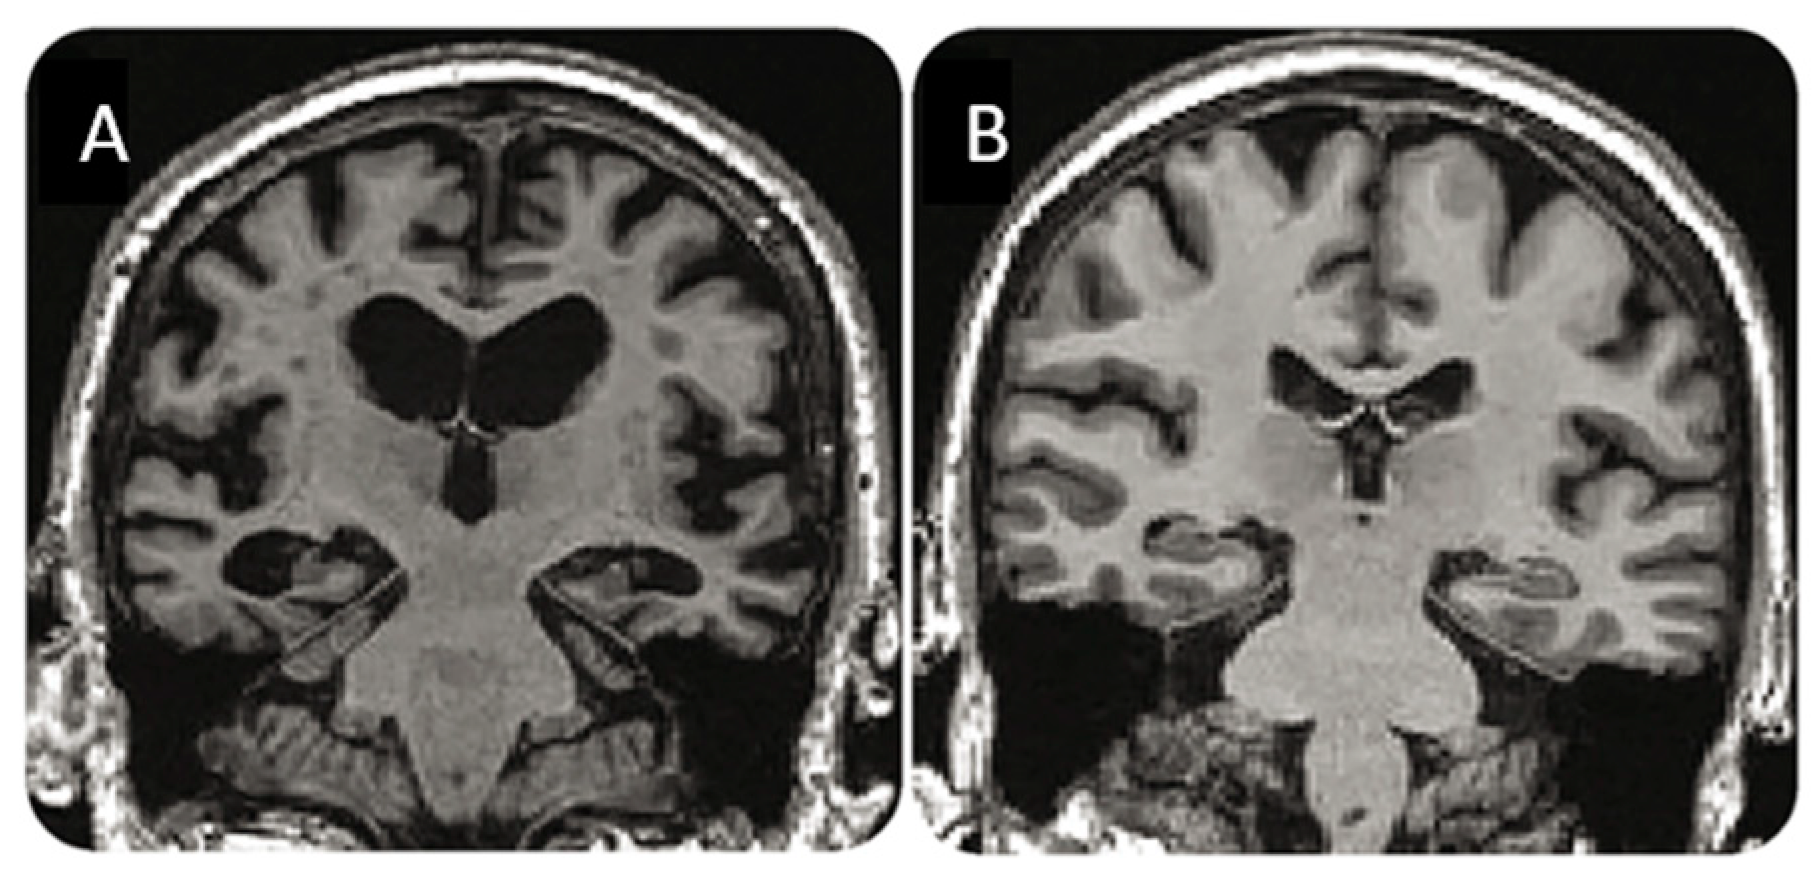

- Høilund-Carlsen, P.F.; Revheim, M.E.; Costa, T.; Kepp, K.P.; Castellani, R.J.; Perry, G.; Alavi, A.; Barrio, J.R. FDG-PET versus Amyloid-PET Imaging for Diagnosis and Response Evaluation in Alzheimer’s Disease: Benefits and Pitfalls. Diagnostics 2023, 13, 2254. [Google Scholar] [CrossRef] [PubMed]